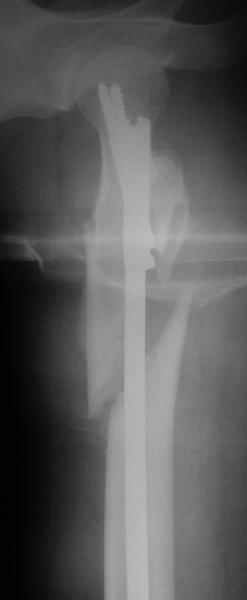

a> Диагноз Закрытый оскольчатый подвертельный перелом правой

a> бедренной кости со смещением отломков,

a> оскольчатый перелом большого вертела, отрывной перелом малого вертела.

Наверно, можно и так сказать, но можно и тоже самое - 4-фрагментный вертельный перелом. Выбор тот же, но с учетом молодого возраста реконструкционный гвоздь тут более применим. Вот уже наш пример.